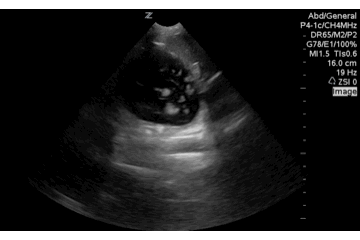

This image was mis-interpreted as a possible splenic injury during a FAST in the LUQ of the abdomen. If the user had pointed the ultrasound beam more posterior in the patient, to where dependent fluid should be they would notice the fluid filled stomach disappear out of view. Not free intraperitoneal fluid, but may be useful to note prior to intubation or if you are concerned for GI bleed.